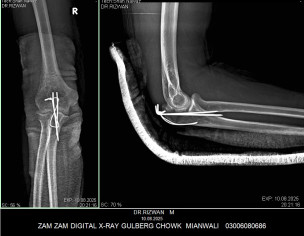

My husband had elbow surgery on 9th of August. I want to know about physiotherapy. When can we start physiotherapy so he can bend and extend his arm freely.Kindly guide us. If we start now will it effect joint or not. TIA

Back slab should be removed and physiotherapy should be started asap with gradual increase in range of motion. otherwise stiffness might occur.

Mostly after 3 Weeks Back slab exchanged with arm and sling and start with protected gentle Range of motion To avoid stiffness

But Final decision will be from operating Surgeon

I would advise you to wait for 6 weeks for elbow Range of motion. keep doing shoulder and wrist ROM from day 1.